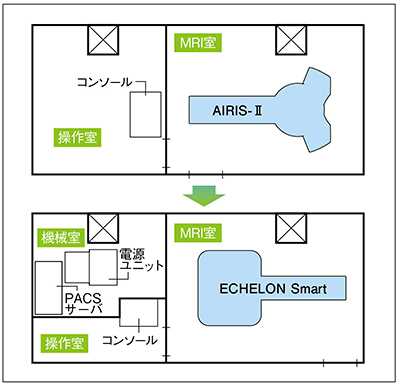

検討では,ECHELON Smartの画像や静音化技術“Smart Comfort”の静音性も評価されたが,最大の決め手となったのが特長の一つである省スペース設計だ。ECHELON Smartは,最小設置面積16m2のコンパクト設計と電源ユニットケーブルの延長によるレイアウトフリーな設計により,永久磁石型オープンMRIが設置できるスペースでも導入可能である。梶原事務長は,「AIRIS-Ⅱが入っていた検査室を拡張することができなかったため,設置スペースの条件をクリアする必要がありました。ECHELON Smartは,MRI室の広さは変えずに操作室のレイアウトを変更することで設置できました」と説明する。

MRI検査室全体のスペースはそのまま,AIRIS-ⅡからECHELON Smartに更新